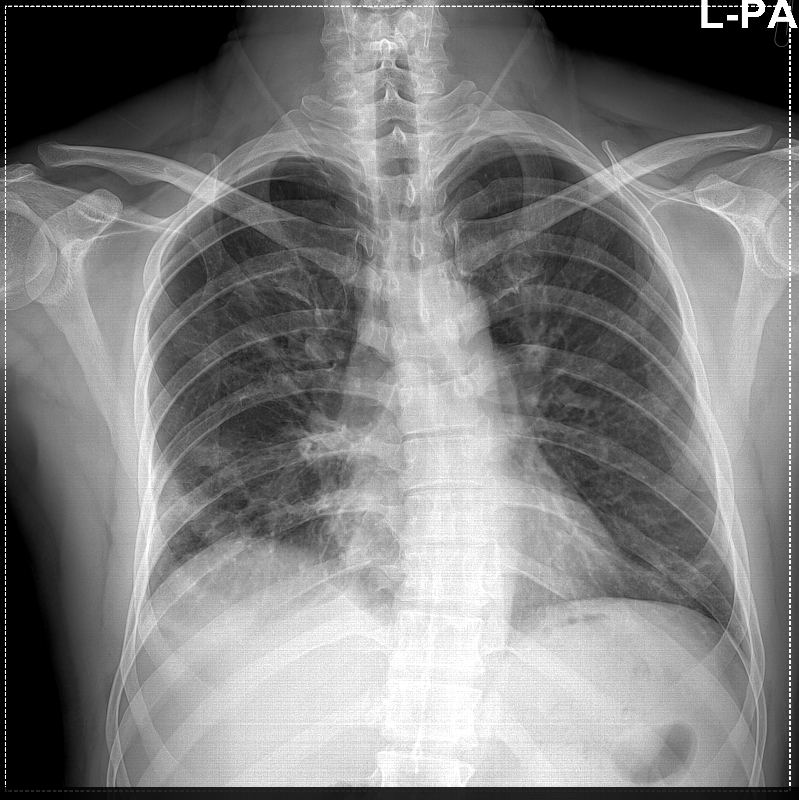

Costochondritis Chest X Ray Can An X Ray Show Costochondritis Repeated minor trauma to your. But a health care provider might order certain tests,. But your provider may use some imaging tests to rule out other causes of rib pain. There is no laboratory or imaging test to confirm a diagnosis of costochondritis. Key sign is pain on. Doctors can usually diagnose a child,. In most cases, doctors don’t know. Can An X Ray Show Costochondritis.

Study Medical Photos Costochondral Calcification Seen On Chest XRay Can An X Ray Show Costochondritis Key sign is pain on. In most cases, doctors don’t know exactly what causes costochondritis, but here are some things that can lead to it: A comprehensive history and physical exam help exclude chest pain etiologies before making a costochondritis diagnosis. Repeated minor trauma to your. There is no laboratory or imaging test to confirm a diagnosis of costochondritis. There’s. Can An X Ray Show Costochondritis.